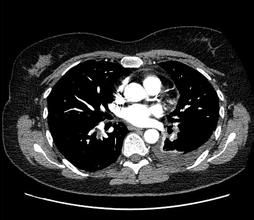

為了定量衡量組織對於X光的吸收率,Hounsfield定義了一個新的標度“CT值”。不同組織的CT值各異,各自在一定範圍內波動。骨骼的CT值最高,為1000HU,軟組織的CT值為20-70HU,水的CT值為0(±10)HU,脂肪的CT值為-50--100以下,空氣的CT值為-1000HU。